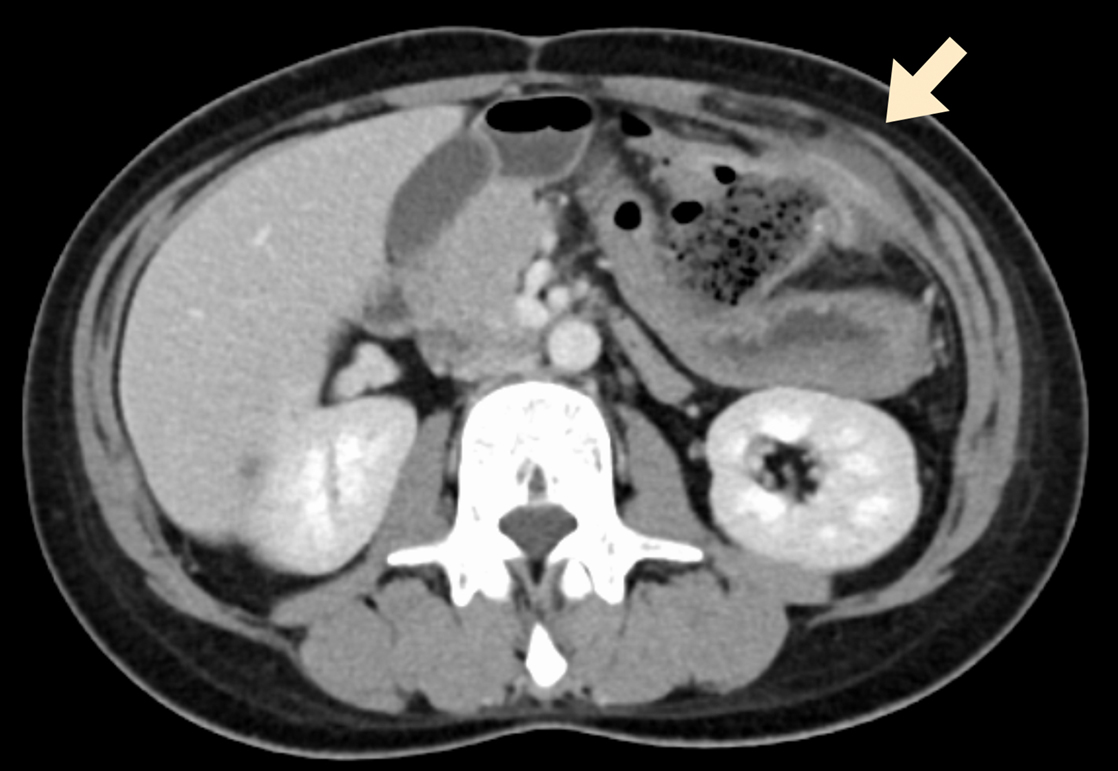

腹部造影CT所見:結腸吻合部周囲に脂肪織濃度上昇があり,左上腹部腹壁に接して境界は不明瞭であった.腹壁内には液体貯留を認めた(Fig. 2).

Contrast-enhanced CT: Fat density increased around the colocolostomy. Fluid collection was observed in the left abdominal wall (arrow). Free air and ascites were not detected.